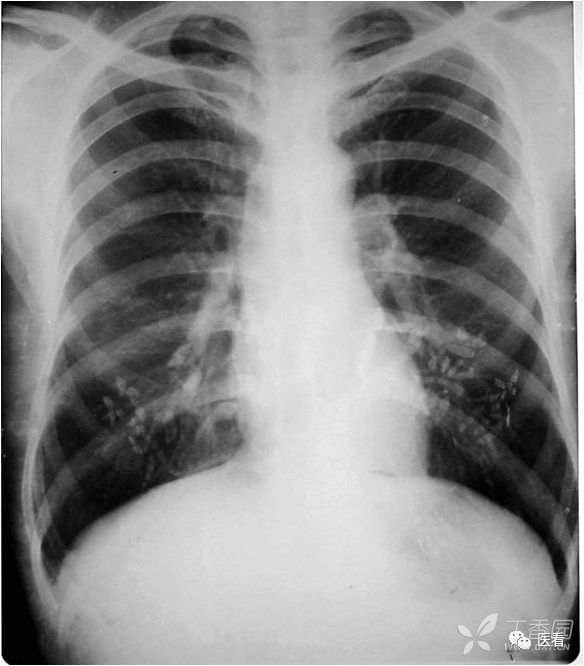

火眼金睛辨真伪:申请单病情摘要:男,44岁,胸痛两天,查体无特殊。

看上去是心脏普遍增大。细心观察,右肺门及右下肺动脉影被掩入增大的心影内(蓝箭头)

本例为食管癌手术后,服用钡餐后,显示实际为胸腔胃(红箭)形成的假象。

真正的心脏增大,肺门及下肺动脉影被向外推移(蓝箭头),在心影外